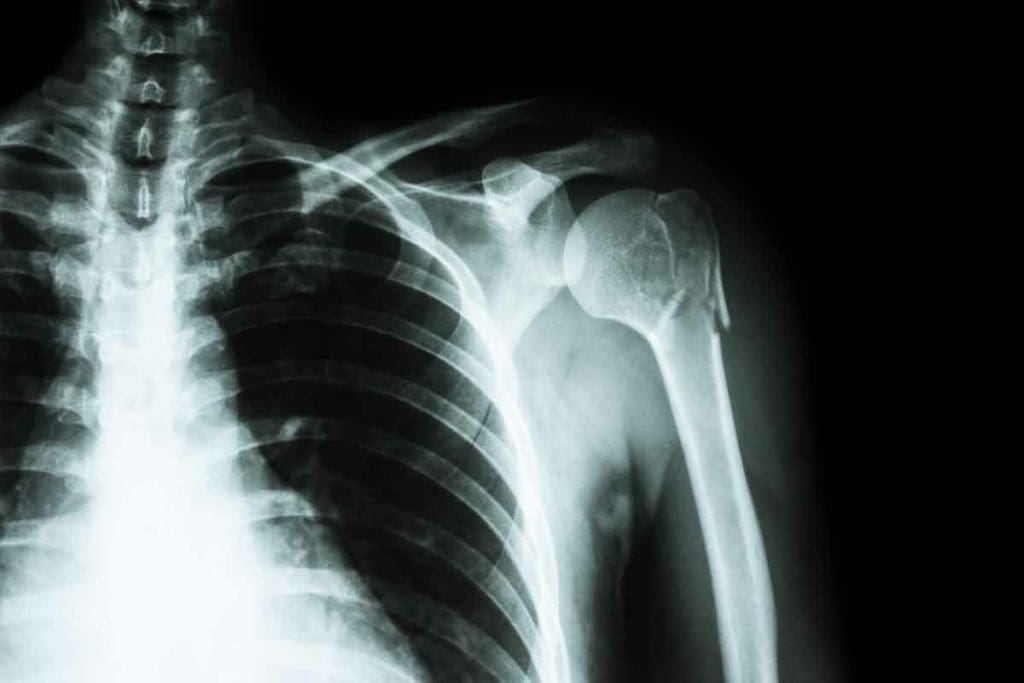

Detecting Bone Fractures and Trauma

Bone scintigraphy is great for spotting fractures that X-rays can’t see. It catches changes in bone activity, helping find hidden fractures.